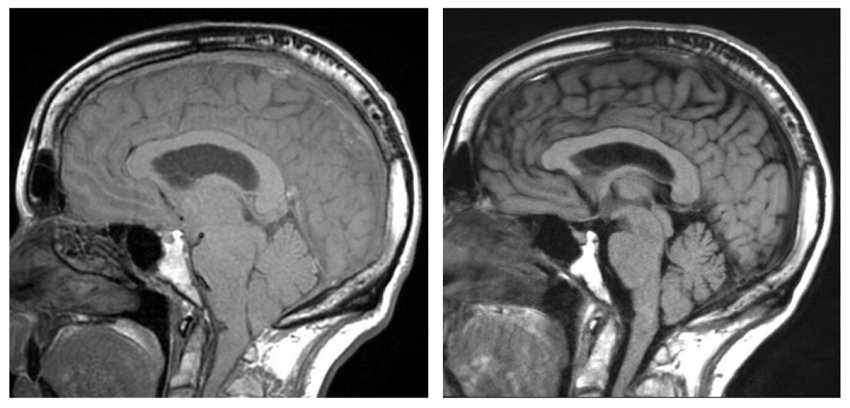

A sinistra scansione di cervello afflosciato, a destra soluzione post-operatoria della flessione

Il liquido cerebrospinale (CSF) circola dentro e intorno al cervello e al midollo spinale per ammortizzare eventuali traumi e ridurre le lesioni. Quando questo fluido fuoriesce nel corpo, il cervello può afflosciarsi, causando sintomi di demenza. Schievink ha affermato che molti pazienti con afflosciamento del cervello (brain sagging), che può essere rilevato dalla risonanza magnetica, restano senza diagnosi e consiglia ai medici di dare una seconda occhiata ai pazienti con sintomi rivelatori.